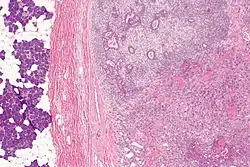

| Micrograph of a carcinoma ex pleomorphic adenoma. The carcinoma component is on the lower right of the image. Benign parotid gland is seen at the left and pleomorphic adenoma is seen at the upper right. H&E stain. | |